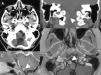

Clinical presentationA 16-year-old female with suspected diagnosis of recurrence of a clear cell meningioma (CCM) at a distance from the initial lesion, located on the premedullary cistern. The patient underwent a pure endoscopic low transclival approach. The attachment to the ventral surface of the brainstem was confirmed intraoperatively. Postoperative MRI confirmed gross total resection and treatment was complemented with adjuvant fractionated stereotactic radiotherapy. No complications related to the procedure were observed.

ConclusionMWODA may appear attached to the ventral brainstem. The expanded endonasal approach to the clivus provides a critical anatomical advantage in the treatment of medial lesions, even ventral meningiomas, to the lower cranial nerves. Reconstruction principles must be strictly respected to reduce complications.